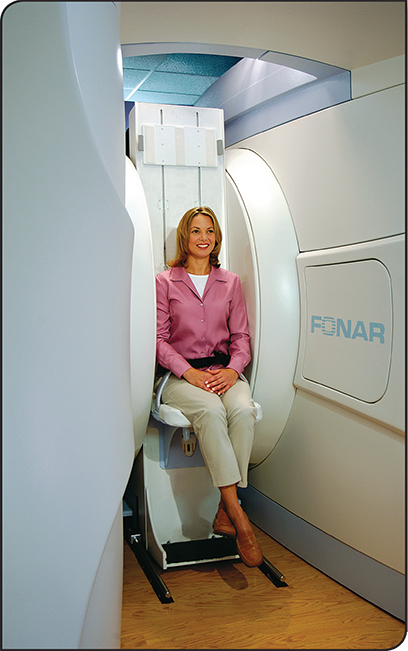

Multi-Positional MRI

The Upright MRI is unlike any other scanner because it can scan patients in ANY POSITION. Other MRI scanners can only scan patients lying down. The Upright MRI can scan patients lying down too, but if the patient has, say, low back pain only when they are sitting or standing, does it make sense to scan them lying down? Only the Upright MRI can scan patients in their positions of symptoms, whatever they may be, including WEIGHT-BEARING positions, such as sitting, standing and bending. This unique ability has enabled the Upright MRI to provide more accurate diagnoses by detecting many problems that were underestimated or completely missed by other kinds of MRI’s.

The Upright MRI is, without a doubt, the most patient- friendly MRI anywhere. Most patients are scanned comfortably seated watching a 42" flat screen tV. The front-open and top-open design of the Upright MRI nearly eliminates possible claustrophobic reactions and enables it to accommodate larger patients.